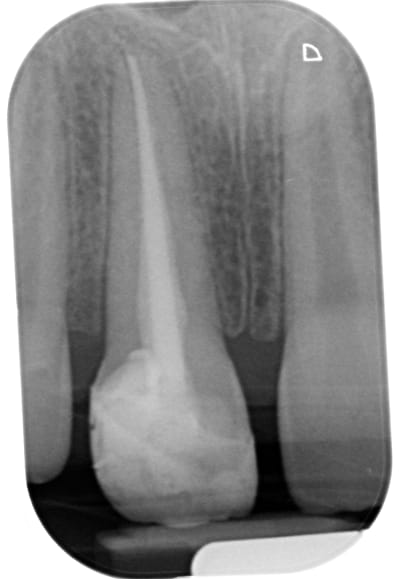

Poser un pangen et coter un comblement c'est du vol. Selon mon CD conseil coter une photo pour justifier ton acte et ou enregistrer tes rapports occlusaux est justifié. bien sur si tu fais un compo de merde dans la salive prendre une photo NR c'est du vol. je pense pas voler mes patients. Les parents du gosse dont je joint le cas n'ont trouvé que je suis un voleur ( malgré les 400 NR) alors qu'ils attaquent le confrère au tarif conventionné.

Difficile a voir sur la radio ; tu as mis un pivot?,

5inon, je pense qu'ils vont attaquer deux dentistes!

A ce stade une dent provisoire et zou!